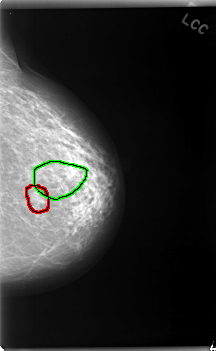

C_0038_1.LEFT_CC

FILE: C_0038_1.LEFT_CC.OVERLAY

TOTAL_ABNORMALITIES 2

ABNORMALITY 1

LESION_TYPE MASS SHAPE OVAL MARGINS ILL_DEFINED

ASSESSMENT 4

SUBTLETY 3

PATHOLOGY BENIGN

TOTAL_OUTLINES 1

BOUNDARY

ABNORMALITY 2

LESION_TYPE CALCIFICATION TYPE FINE_LINEAR_BRANCHING DISTRIBUTION CLUSTERED

ASSESSMENT 5

SUBTLETY 4

PATHOLOGY MALIGNANT